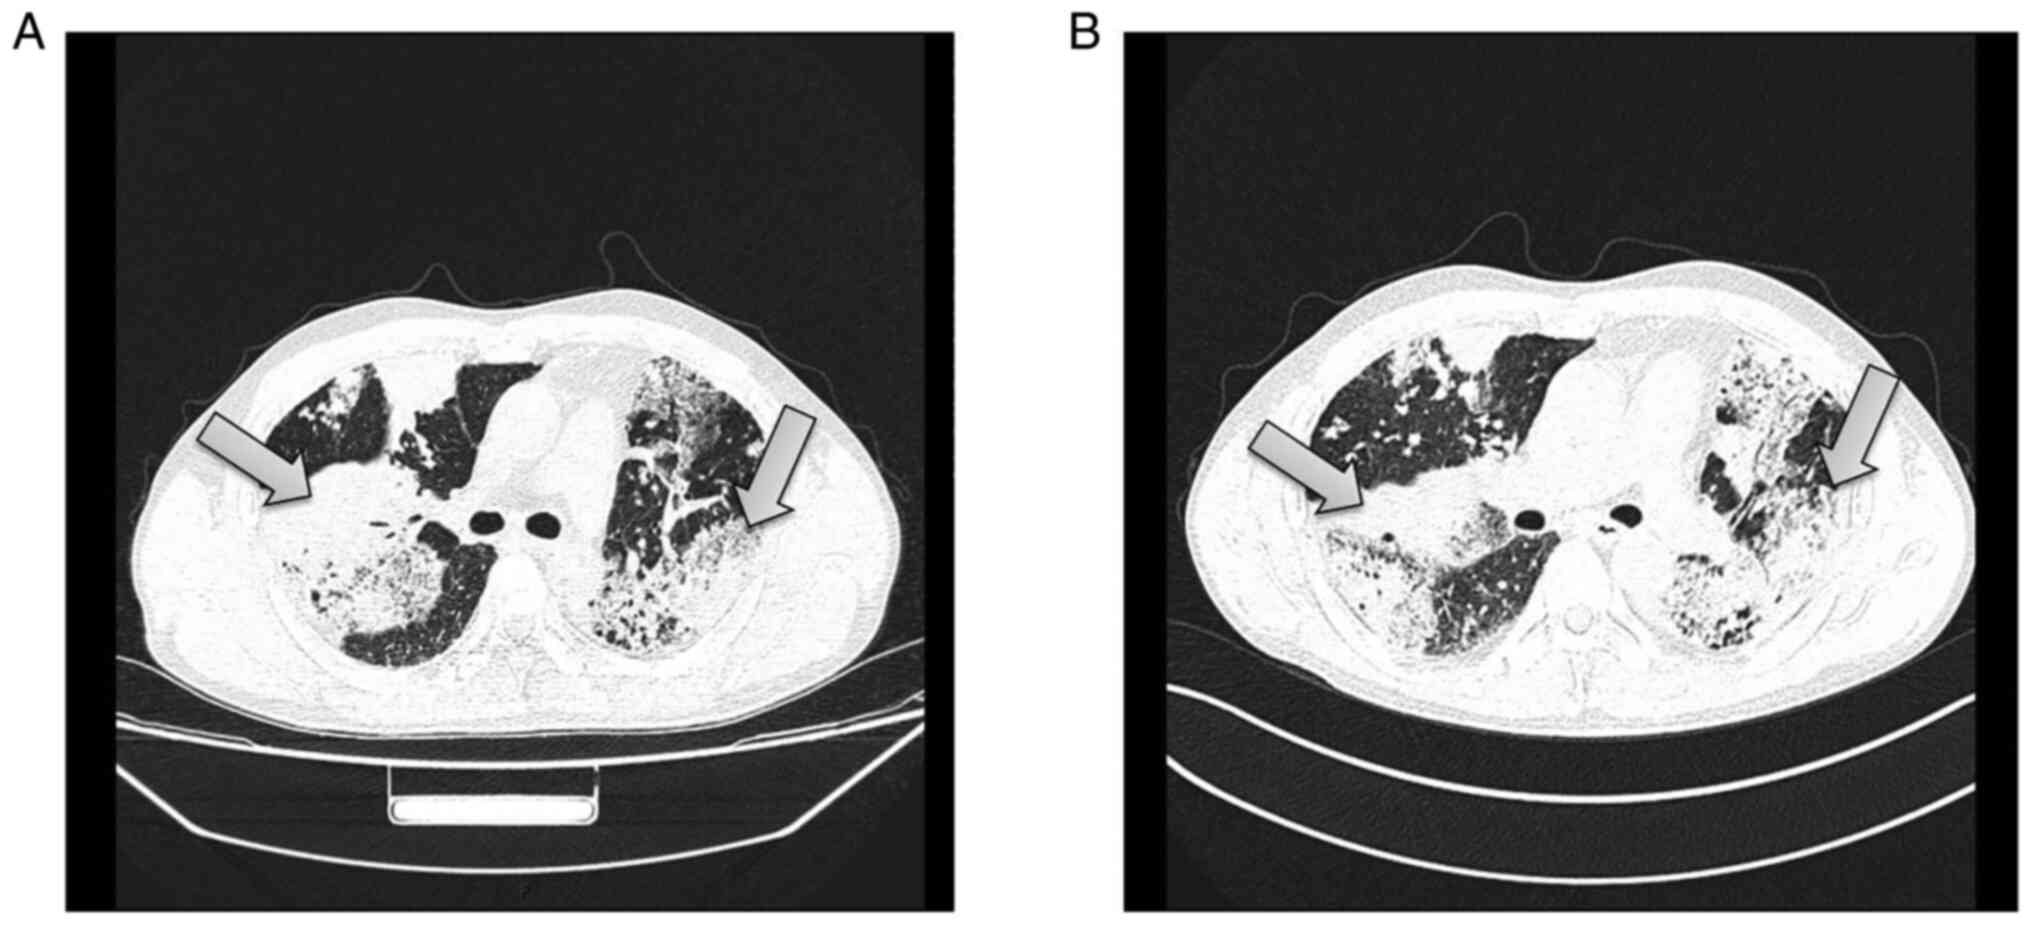

His vital signs were within normal limits. Physical examination revealed coarse breath sounds and scattered wet rales in the bilateral lungs. Laboratory tests at admission included white blood cell count (0.42x109/l), percentage of lymphocytes (12.1%), and percentage of neutrophils (80.1%). His C-reactive protein level was 5.4 mg/l, and his erythrocyte sedimentation rate was 20 mm/h. T-SPOT for tuberculosis infection was positive, with 84 spots in panel A and 18 spots in panel B. A tumor marker test showed the following: Carcinoembryonic antigen, 48.15 ng/ml; carbohydrate antigen 19-9, >400.00 U/ml; carbohydrate antigen 153, 75.49 U/ml; carbohydrate antigen 242, >200.00 U/ml; cytokeratin 19-fragment, 5.19 ng/ml; and carbohydrate antigen 72-4, 70.33 U/ml. Renal function, electrolyte level, and blood coagulation function were in the normal ranges. Chest CT showed the following: i) Diffuse, patchy and blurry hyperdense shadows, nodular shadows and patchy consolidation, which were more obvious in the right upper lobe and left lung; the image findings suggested a suspected infectious lesion, but other lesions could not be ruled out; ii) multiple lymph nodes with partial calcification in the mediastinum and the lungs; and iii) minor effusion in the left thoracic cavity and bilateral pleural thickening (Fig. 2A). Enhanced chest CT showed: i) diffuse, patchy and blurry hyperdense shadows and nodular shadows that were more obvious in the right upper lobe and left lung; enhancement of CT was not clear, the image findings suggested a suspected infectious lesion, but other lesions could not be ruled out; ii) multiple lymph nodes with partial calcification in the mediastinum and the lungs; and iii) minor effusion in the left thoracic cavity and bilateral pleural thickening (Fig. 2B).

Figure 2

CT scan of the chest. (A) CT and (B) enhanced CT of the chest. Arrows indicates the shadow in the upper lobe of the right and left lungs. CT, computed tomography.

The patient received empiric antimicrobial therapy following admission. Combined cefuroxime sodium (0.75 g/8 h, intravenous injection) and moxifloxacin hydrochloride (0.4 g/day, intravenous injection) were administered for anti-infection treatment. According to the results of chest CT and enhanced chest CT, it was possible to consider infectious lesion. At one week following anti-infective treatment, chest DR examination showed that the lesions were more advanced than before (Fig. 1B). The T-SPOT test was positive but with a small number of spots. The possibility of tuberculosis was low. The patient's tumor marker levels were significantly elevated. IMA could not be ruled out. Thus, fiberoptic bronchoscopy was performed and found no obvious morphological change (Fig. 3). The pathological examination suggested that the mucosal epithelium was undergoing chronic inflammatory changes with mucosal epithelial cell proliferation (data not shown). A case discussion in Departments of Pulmonary and Critical Care Medicine, The First Affiliated Hospital of Chengdu Medical College considered a tumor diagnosis according to the tumor marker and pathology results. A percutaneous lung puncture biopsy was performed (Fig. 4A). The collected samples were fixed in 10% neutral buffered formalin 24 h at room temperature and embedded in paraffin. Sections were cut at 5 µm and hematoxylin-eosin and thyroid transcription factor 1 (TTF-1) immunohistochemical (IHC) staining (6) were performed following the manufacturer's protocols. The adenocarcinoma was diagnosed based on the pathological staining which were evaluated independently by two pathologists at the First Affiliated Hospital of Chengdu Medical College in a double-blinded manner (Fig. 4B and C). Pathological specimens were almost negative for all driver genes, except KRAS (Table I). However, there was no KRAS G12C molecular targeted drug in 2019 and the patients and family refused treatment, including chemotherapy, radiotherapy and interventional chemotherapy and the patient was discharged from the hospital.